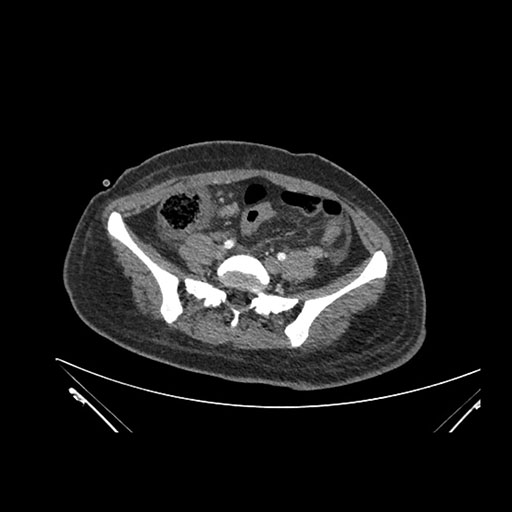

Imaging Analysis

Look through the patient's CT scan to identify any areas of concern for the necessary procedure.

Axial Arterial

Based on initial findings, which issue(s) would you be most concerned about?